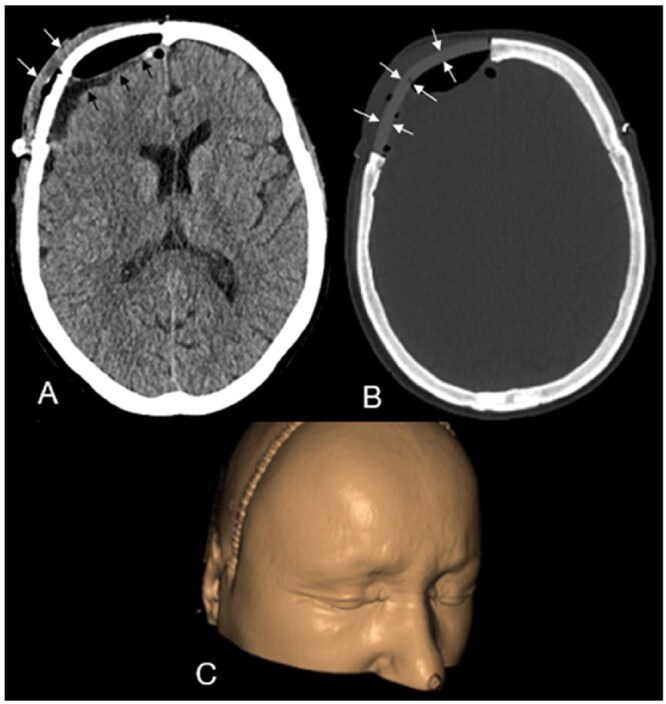

Primary central nervous system (CNS) mucosa-associated lymphoid tissue (MALT) lymphoma is a rare condition frequently mistaken for meningioma. Since these conditions require distinct treatment approaches, recognizing their imaging characteristics is essential for accurate clinical decision-making. A 69-year-old woman presented with headaches and forehead swelling, prompting MRI of the CNS. Suspecting an intracranial meningioma, the tumour board recommended surgical resection. However, histopathological analysis identified the lesion as a primary CNS MALT lymphoma. Follow-up revealed secondary cutaneous tumour infiltration, leading to a delay in adjuvant radiotherapy. Understanding the differential diagnoses of meningioma is critical for neuroradiologists and neurosurgeons to ensure appropriate treatment planning. This case highlights a misdiagnosis of meningioma that was ultimately identified as a primary CNS MALT lymphoma, emphasizing key imaging and clinical characteristics essential for distinguishing between the most important differential diagnoses of primary CNS MALT lymphoma.